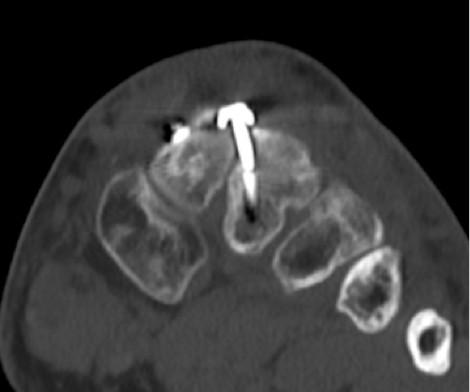

Im CT vom September 2017 ergab sich noch kein Durchbau der Arthrodesen, aber ein Bruch der das TMT 2 überbrückenden Schraube.

6.- 09/2017 Schraubenbruch

Durch die Fehlplatzierung der Plattenschraube ist es zu einem erwarteten Schraubenbruch in Höhe des 2.Mittelfußgelenkes gekommen. Die abgebrochene Schraube überragt die Gelenkfläche des 2.Mittelfußstrahls und führt dort zu einer mechanischen Irritation mit zwingend nachfolgender Verschleißerkrankung, die aus dem Vergleich der CT Aufnahmen von 19.04.2018 und September 2017 bereits deutlich zu erkennen ist.